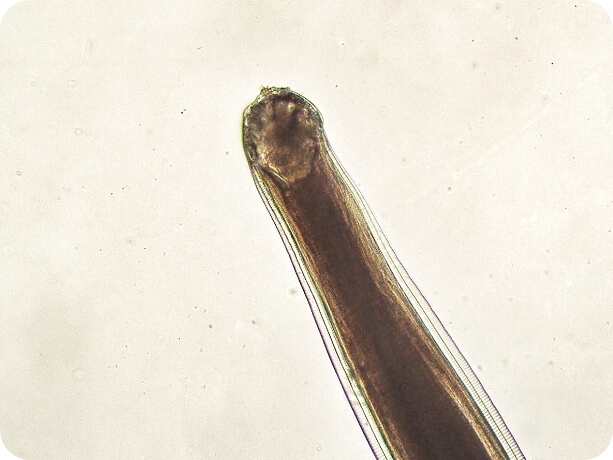

Image of a hookworm up close

Hookworms

Hookworms are intestinal parasites that can live in your dog’s digestive system. True to their name, they attach themselves to the intestinal wall by literally hooking onto the tissue. Hookworms feed on a dog’s blood and eject their eggs into the digestive tract, which allows them to be passed into your dog’s environment via their feces.1